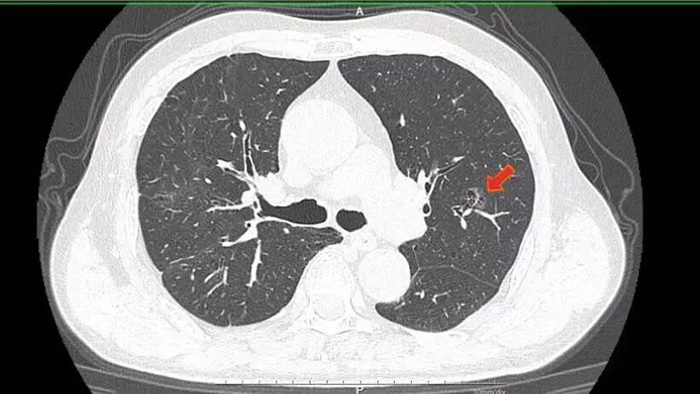

▲术前胸CT 我院胸外科医疗团队在仔细检查后发现,李大爷的肺占位长在左肺上叶中间,是典型的混合性磨玻璃结节。要是按照传统胸腔镜手术方式,要么得切除整个左肺上叶,要么就得切掉左肺上叶尖后段,对本就肺功能不佳的李大爷来说,无疑是雪上加霜。考虑到他的复杂病史和全身状况,王勇智副院长带领科室副主任裴帅等专家团队成员立刻开展周密讨论,只为找到最优治疗方案。

借助mimics三维重建技术,医疗团队清晰看到:李大爷的病灶位于左肺上叶尖后段的c亚段,且以磨玻璃成分为主,实性成分占比还不到25%。结合这一特点,为了最大程度保留肺功能,同时确保手术能达到根治效果、保留足够切缘,团队最终敲定了荧光胸腔镜“流域法”S1+2c精准肺段切除方案——这一方案,相比传统治疗,更是给李大爷带来了三大实打实的好处。